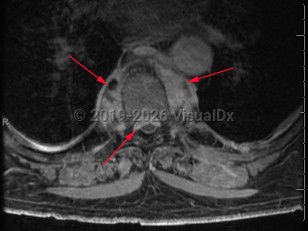

Paraspinal abscess

Paraspinal abscess is a collection of pus located around the spinal cord. This is usually seen as a complication of vertebral osteomyelitis and discitis (diskitis) but may be related to hematogenous seeding during bloodstream infection. Epidural catheters and injections may lead to direct inoculation of the epidural space. Frequently, the location of the abscess is in the epidural space.

Patients may have acute (develops over hours) or subacute (develops over weeks to months) back pain. Fever may or may not be present. As the abscess forms, patients typically have focal and severe back pain. As the size of the abscess increases, it may impinge on the spinal cord, leading to signs of spinal cord compression, including motor weakness and sensory deficits. Untreated, the patient's neurologic symptoms can worsen to the point of irreversible paralysis.